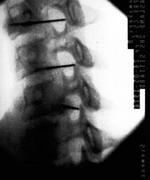

Con el paciente en decúbito supino y el cuello en ligera hiperextensión, se realizan 4 movimientos con el arco de rayos (Rx). Con el Rx en posición lateral, se identifica el nivel que se va a tratar. Cuando se ha identificado, se realiza un movimiento del Rx en posición oblicua hasta que se visualiza el foramen completamente. Cuando el foramen se ve claramente, se realiza un movimiento craneocaudal para eliminar el doble contorno del agujero que se va a tratar. Por último, con una proyección anteroposterior, se debe visualizar la punta de la aguja en la porción media de la articulación facetaria.